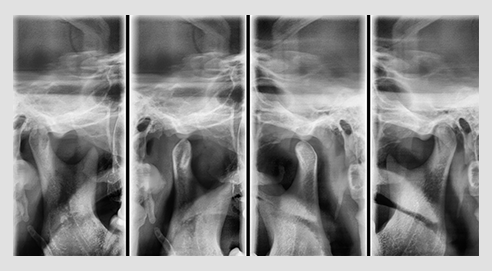

The PaX-i has various capture modes to meet your diagnostic needs.

You can choose any capture mode based on your diagnostic needs.

| SELECTION | ARCH | EXAMINATION MODE |

|---|---|---|

| PANO EXAMINATION | Narrow / Normal / Wide / Child | Standard / Right / Front / Left |

| PANO EXAMINATION | Orthogonal | Orthogonal Standard / Right / Front / Left Bitewing Standard / Right / Front / Left |

| SPECIAL EXAMINATION | Normal | TMJ LAT Open / Close TMJ PA Open / Close Sinus LAT / PA |